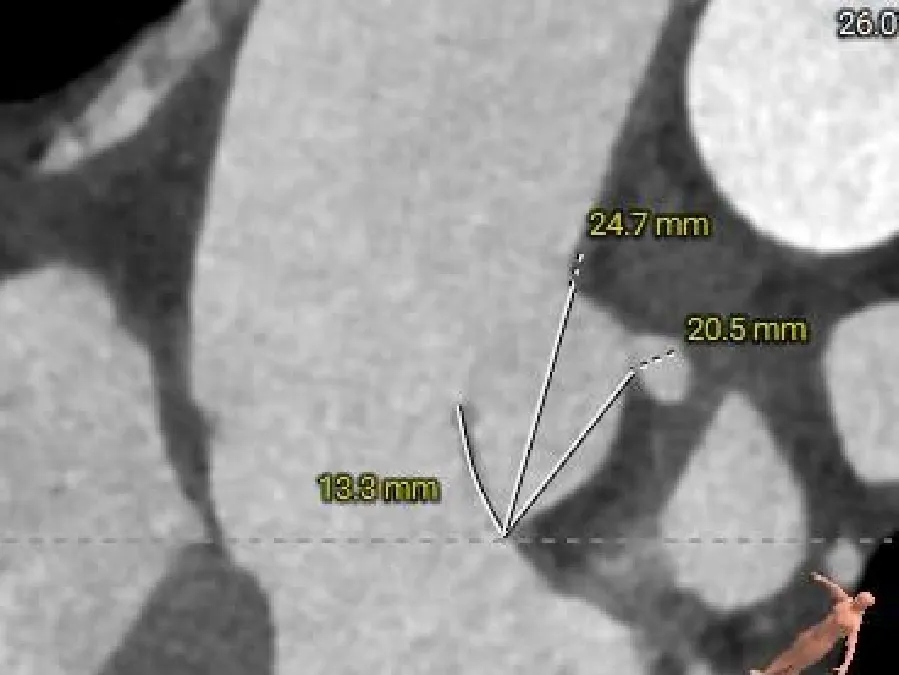

术前CT分析

主动脉根部测量

Annulus

25.9mm

LVOT

29mm

SOV

37.4*34.1*35.3mm

STJ

33.9mm

AAO

38.4mm

心脏角度

49°

纯反流三叶瓣,瓣环内径25.9mm

流出道敞口型

瓣叶轻微增厚、无钙化

瓦氏窦、STJ、升主内径可

瓣上结构测量

瓣上2mm

25.7mm

瓣上4mm

瓣上6mm

26.2mm

瓣上8mm

27.3mm

瓣上锚定空间逐渐增大